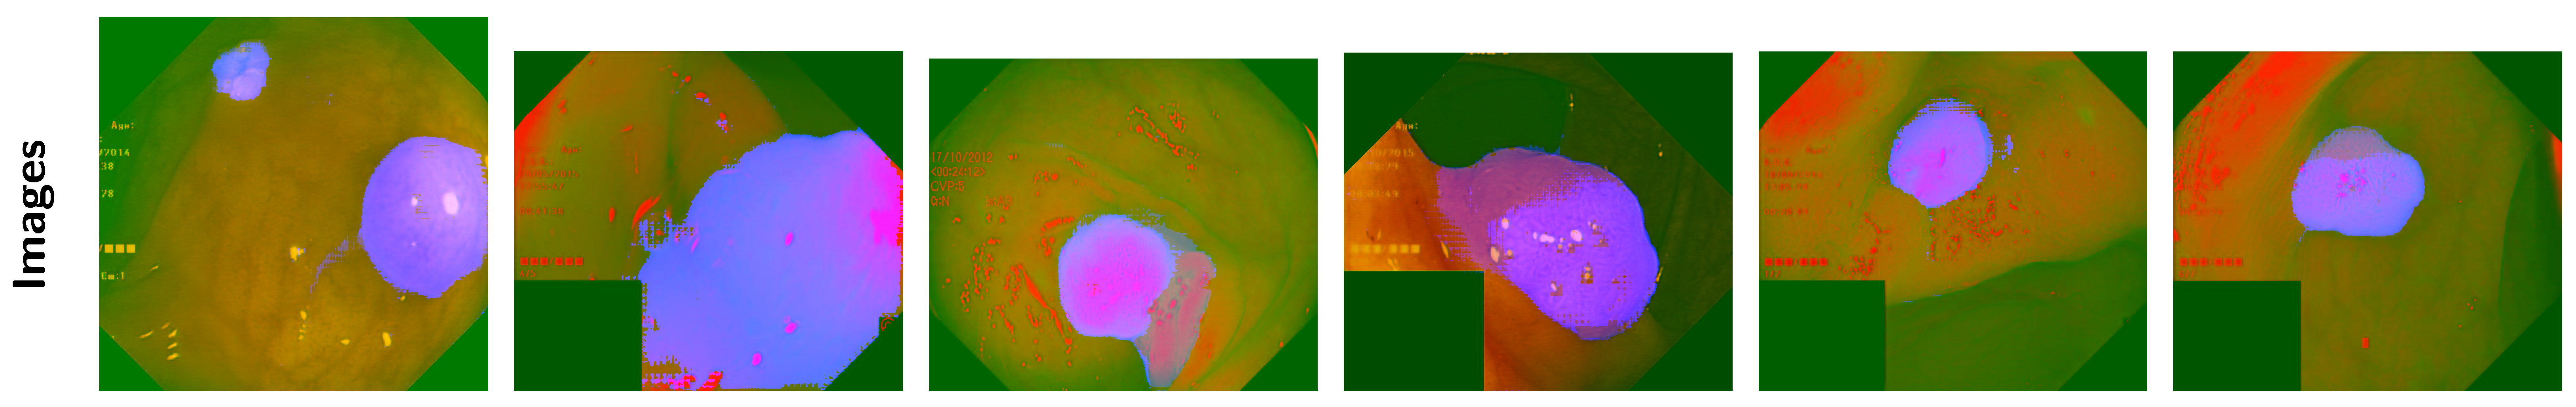

2.3.5. PCA-segPrior

- Segmentation Mask Generation: The algorithm begins by generating segmentation masks using a mask generator. These masks represent regions of interest within the image, and each mask is associated with a stability score, which indicates the confidence in the mask’s correctness.

- Segmentation Prior Calculation: The matrix is initialized as a blank matrix (zeros). Then, for each segmentation mask, the algorithm updates . This update involves multiplying each mask by its corresponding stability score and accumulating the results. The segmentation prior thus reflects the confidence in various regions of the image based on the available segmentation masks.

- Dimensionality Reduction via PCA: The image is subject to PCA to reduce its dimensionality from three channels (RGB) to two channels. The reduced representation captures the key features of the image in fewer dimensions, making it more efficient for further processing.

- Scaling of PCA and Segmentation Data: The PCA output and the segmentation prior are normalized to the range to ensure that the data are properly adjusted for visualization and processing.

- Image Reconstruction: The image is reconstructed by combining the scaled PCA results and the segmentation prior into the red, green, and blue channels of the image. The red and green channels come from the PCA output, while the blue channel is influenced by the segmentation prior. This modified image now encodes both the reduced-dimensional representation of the image and additional information from the segmentation.